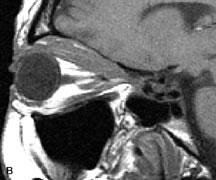

PATIENT PREPARATION Before MRI is performed, patients must be screened and prepared to avoid the potential hazards associated with the strong magnetic field. Patients who have ferrous aneurysm clips or cardiac pacemakers, who depend on life-support equipment, or who retain a possible metallic intraocular foreign body are not candidates for this imaging modality. MRI cannot be performed on obese patients who cannot fit into the bore of the magnet. Patients who are claustrophobic may not tolerate a prolonged period of study within the confines of the magnet, whereas others might do well if given a mild sedative. All worn metallic objects (e.g., necklaces, watches) should be taken off, credit cards set aside, and eye makeup removed before entering the room containing the magnet.5,20,34,35,36 NORMAL ORBITAL ANATOMY T1-weighted images provide the best anatomic details of the orbit because they display superior contrast resolution between normal structures (see Fig. 8). The vitreous has a long T1, resulting in an intermediate signal similar to brain, whereas the crystalline lens and sclera appear dark because of a longer T1 and short T2. The extraocular muscles, like all skeletal muscles, demonstrate a moderately long T1 and short T2 and highly contrast with the intense signal of the surrounding orbital fat (adipose tissue has an extremely short T1). The lacrimal glands appear as mottled areas of reduced intensity of the signal from the orbital fat in the lacrimal fossa. The optic nerves are seen with the same signal intensity as brain white matter and are hypointense relative to the orbital fat because their Tl is longer than the Tl of fat but shorter than the Tl of water. Cortical bone is not well delineated because it contains little free water, yielding minimal signal in MRI, and thus appears dark on all pulse sequences. This feature explains why MR images of the orbital apex and intracanalicular portion of the optic nerves are superior to comparable CT scans. Partial volume averaging of the bones in these regions obscures soft tissue details on CT images, whereas MRI reveals the signals only from the soft tissue structures with no cortical bone input. Bone marrow, on the other hand, is seen as a relatively intense signal because of its high fat content (see Fig. 8).37,38 T2-weighted pulse sequences are not ideal for imaging normal anatomy; however, they are particularly useful in revealing pathologic conditions (see Fig. 9). T2-weighted studies are most easily recognized by a bright vitreous signal. ORBITAL DISEASES Vascular Lesions Cavernous hemangiomas appear as well-circumscribed, smooth, usually intraconal masses that are isointense to muscle on T1-weighted images and hyperintense on T2-weighted images (Fig. 12). Patchy early enhancement is typically followed by diffuse, more homogeneous enhancement.39 The internal architecture of the mass, including septation and internal vasculature, may often be appreciated with high-quality orbital imaging.40 Lymphangiomas consist of ectatic vascular channels within a connective tissue stoma with varying degrees of lymphoid cellularity. On MRI, these tumors are typically poorly circumscribed, multicompartmental, and heterogeneous, often showing cystic dilations with fluid levels (Fig. 13). The signal characteristics within lymphangiomas vary considerably, reflecting cystic and solid components and the varying paramagnetic characteristics of blood at different stages of degradation.40–42 Acute hemorrhage appears hypointense on both T1- and T2-weighted formats. Methemoglobin present in subacute hemorrhage (3 to 14 days) leads to hyperintense signal on both T1- and T2-weighted images.41 A small percentage of lymphangiomas appear radiologically indistinct from orbital cavernous hemangiomas.43 Orbital varices are venous malformations that expand with increased systemic venous pressure, such as with Valsalva maneuvers. Because rapid acquisition of images during a Valsalva maneuver is important in imaging such a lesion, conventional or spiral CT is currently the modality of choice.44 MRI is an excellent modality for demonstrating enlargement of the cavernous sinus and dilation of the superior ophthalmic vein in patients with high-flow carotid-cavernous fistulas (Fig. 14).37MRA may be helpful in the evaluation of the venous outflow pattern. The rapidly flowing blood in these vascular structures carries the excited protons out of the section before they can be imaged, resulting in their dark appearance.5 In low-flow dural arteriovenous malformations, MRA may help define the arterial feeding vessels.45 Neural Lesions MRI is more effective than CT in delineating the intracranial optic nerves, chiasm, and optic tracts and, for this reason, is the preferred imaging modality in the evaluation of optic nerve disorders. The spatial relationships and image contrast of the orbital tissues with intraorbital optic nerve tumors is comparable between the two imaging modalities. The normal nerve is isointense to brain and appears enlarged and kinked owing to infiltration of an optic nerve glioma on T1-weighted images. Gliomas appear hyperintense on T2-weighted images and may be heterogeneous owing to cystic areas within the tumor. Contrast enhancement is variable.46 Intraorbital and intracranial optic nerve sheath meningiomas are usually isointense to cortical gray matter on Tl-weighted images and remain isointense on proton density studies (Fig. 15). Gd-DTPA is useful in delineating the intracranial extension of optic nerve meningiomas.7,47 The hyperostosis of bone and calcification associated with meningiomas are not demonstrated as well on MRI studies as on CT scans.20,37 Gd-DTPA–enhanced MRI also appears promising in the study of the permeability of the blood–brain barrier in selected optic neuropathies.22,48 MRI may reveal an enlarged optic nerve and some degree of contrast enhancement in cases of optic neuritis.49 Muscle Disorders Extraocular muscle enlargement in patients with thyroid-associated orbitopathy is demonstrated equally well with CT and MRI studies. However, the superior tissue contrast on MR images reveals better details of the relationships of the optic nerve to the thickened muscles at the orbital apex (Fig. 16).50 In addition, MRI may be able to differentiate between muscles that are enlarged as a result of edema and active inflammation and those enlarged because of fibrosis by their T2 relaxation times.21 Quantitative MRI was not found to be accurate in predicting the success of low-dose orbital irradiation.51 However, a muscular index relating the diameters of the rectus muscles to the bony orbital dimensions was useful in predicting optic nerve compression.52 MRI is also effective in imaging orbital tumors of mesenchymal origin, such as rhabdomyosarcoma, particularly in the assessment of extension into the anterior and middle cranial fossae (Fig. 17).37 The lack of any pathognomonic radiologic features necessitates rapid orbital biopsy when rhabdomyosarcoma is suspected. Osseous Lesions In general, CT is the imaging modality of choice when details of quantity and quality of bone are needed; however, abnormalities of bones can be detected indirectly by MRI. Cortical bone appears black (signal void) on MR images because of its low proton density and free-water content. The absence or discontinuity of the signal void of the orbital walls may represent bony destruction or fracture. Hyperostosis associated with prostate metastases or meningioma is visualized as areas of black smudging.50,53 Diseases in which the bone is replaced by pathologic tissues with a high free-water content, such as fibrous dysplasia, are well demonstrated on MRI. An intermediate signal intensity on T1-weighted images and hypointense signal on T2-weighted images is representative of fibrous dysplasia. Enhancement on post–Gd-DTPA MR scans is seen and is more evident in areas that are less mineralized.54 Cystic Lesions Dermoid cysts appear as rounded, well-defined lesions typically contiguous with an orbital bony suture. The high-intensity signal on T1-weighted images is attributed to the sebaceous-produced lipid contents (Fig. 18).31,50 Mucoceles may demonstrate a hypointense or hyperintense signal on MR images, depending on the concentration of proteinaceous or inflammatory fluid components. The integrity of the bony walls of the expanded sinus cavities cannot be assessed on MR as well as by CT.37,50,55,56 A high-signal intensity on Tl- and T2-weighted images is characteristic of orbital chronic hematic cysts because of the blood-breakdown products within the cysts.57 Trauma Although soft tissue relationships are usually better demonstrated on MRI, the evaluation of craniofacial bony trauma is preferable with CT. For example, prolapse of orbital fat through a fracture site and hemorrhage of adjacent tissues are demonstrated in an MR image, but the actual fractured bone is not imaged. Three-dimensional MRI of the orbit in subacute trauma has been described,58 although its precise role is not currently established. MRI has been suggested to be superior to CT in detecting intraorbital wooden foreign bodies.59,60 In a series of penetrating orbital injuries with organic foreign bodies, however, MRI was able to identify the foreign body in only four of seven cases.61 With an in vitro model for wood foreign body, McGuckin and colleagues concluded that CT was the imaging modality of choice.62 A careful history and, in selected cases, plain films to rule out a metallic foreign body are crucial before MRI is considered in patients with periocular trauma. MRI is particularly helpful in the detection and characterization of subperiosteal hematomas of the orbit (Fig. 19). They are most commonly seen in the subperiosteal space of the superior orbit as well-defined masses following a traumatic injury. The signal intensity varies depending on the acute, subacute, or chronic nature of the hematoma, based on the stage of blood degradation. Fresh hemorrhages are hypointense on T1-weighted images and hyperintense on T2 images. Hematomas that are 1 to 7 days old are hypointense on both T1- and T2-weighted images. T1-weighted images of hematomas more than a week old are hyperintense due to the oxidation of deoxyhemoglobin to methemoglobin, whereas the T2 images remain hypointense.63 Metastatic Tumors Breast carcinoma metastatic to the orbit has been demonstrated to be hypointense to the surrounding orbital fat on T1-weighted studies and hyperintense on T2-weighted images and has an affinity to the extraocular muscles (Fig. 20).50,64 The MRI characteristics of prostate carcinoma metastatic to the orbit have been described as involving the greater and lesser wing of the sphenoid, orbital roof, and optic canal. Diffuse bone hypertrophy with isointense or slightly hyperintense tissue on T1-weighted images represents the osteoblastic carcinomatous bone infiltration. Contrast enhancement is variable on T1-weighted and fat-suppressed images.65 Most other metastatic tumors also have a lower intensity signal on T1-weighted images and appear to displace or infiltrate normal orbital structures; however, their signal characteristics are variable on T2-weighted MR images.66 Many metastatic tumors demonstrate bright contrast enhancement with Gd-DTPA. Infectious Disorders MRI findings of preseptal and orbital cellulitis typically include increased signal intensities on T2-weighted images of the eyelids and orbital fat, respectively, due to the increased water content of the tissues. Since most cases of bacterial orbital cellulitis are associated with paranasal sinusitis, hyperintense signals of the affected sinuses may also be found on T2-weighted images as well as enhancement of polyps and granulation tissue on postgadolinium T1-weighted MR images. Subperiosteal abscess formation may occur due to contiguous spread of infection from the paranasal sinuses and appear on MRI as an area of intermediate signal on T1-weighted and proton-weighted MR images. The abscess may appear slightly hyperintense compared with muscle on T2-weighted scans with the necrotic contents having the greatest intensity.67 MRI and MRV are more sensitive than CT in revealing cavernous sinus thrombosis. Engorgement of the cavernous sinus, extraocular muscles, and ophthalmic veins is seen with hyperintensity of the thrombosed sinuses evident on all pulse sequences. The enlarged, thrombosed superior ophthalmic vein appears less hypointense than the normal contralateral ophthalmic vein, and hyperintensity within the lumen of the vessel may be seen on T1- and T2-weighted MR images.68 Inflammatory and Lymphoproliferative Lesions Inflammatory conditions of the orbit, both idiopathic (inflammatory pseudotumor) and those of known causes, have been found to be hypointense to fat and isointense to muscle on Tl-weighted studies and isointense or slightly hyperintense to fat on T2-weighted images (Fig. 21).50,64,69 The more fibrous or sclerosing varieties have less signal intensity on T2-weighted images. Marked enhancement is seen in pseudotumor infiltrates after gadolinium administration.70 The same signal characteristics are demonstrated in patients with Tolosa-Hunt syndrome, with mass lesions seen in the cavernous sinuses and orbital apices.71 Lymphomas have MRI characteristics similar to those of inflammatory lesions in that they are hypointense to fat and isointense to muscle on T1-weighted images (Fig. 22). They may appear hyperintense to fat on T2-weighted images, perhaps owing to less fibrosis than that seen in orbital inflammatory pseudotumor, although this is not a consistent finding.31,50,66 Lymphoid tumors typically enhance moderately after contrast injection. Unfortunately, studies have shown that tumor density and homogeneity are similar between inflammatory and malignant orbital infiltrates, and MRI cannot differentiate these lesions.72,73 Lacrimal Gland Tumors Lacrimal gland lesions present special problems in diagnosis and management. Pleomorphic adenoma (benign mixed tumor) should not be biopsied, but rather excised in toto. On the other hand, for lymphoma and inflammatory infiltrates, incisional biopsy is more appropriate than complete excision of the lacrimal gland. Thus, preoperative clinical and radiologic evaluation are especially crucial in planning appropriate surgical management. Pleomorphic adenomas demonstrate long T1 and T2 signal characteristics. They may show heterogeneity on T2-weighted images74 and moderate to marked enhancement with contrast.75 Signal characteristics of adenoid cystic carcinoma include hypointensity to fat on T1-weighted images, hyperintensity to fat with increased T2 weighting, and isointensity to fat on proton density-weighted studies (Fig. 23).31,75 Secondary bony alterations of the lacrimal fossa associated with lacrimal gland tumors, such as remodeling (benign mixed tumor) or destruction (adenoid cystic carcinoma), are seen indirectly on MR images; however, bone windows on CT scans provide better delineation of these changes. In contrast to the round or globular appearance of benign or malignant epithelial tumors of the lacrimal gland, lymphoproliferative tumors usually appear to be molding or draping onto the globe and the surrounding bony orbit. LACRIMAL DRAINAGE SYSTEM DISORDERS MRI with surface coils provides excellent spatial resolution and tissue-specific signal intensities of the lacrimal drainage system. These parameters have been found useful to more accurately demonstrate the extent of lesions in the lacrimal sac and differentiate long-standing mucoceles from solid tumors than CT.76 Physiologic studies in patients with tearing disorders now include MR dacryocystography, in which Gd-DTPA is either placed topically in the conjunctival fornix or injected by cannulation into the lacrimal sac. They provide a detailed morphologic and functional analysis of the lacrimal excretory system; however, they are no more sensitive than digital-subtraction dacryocystography or CT dacryocystography.77–79 INTRAOCULAR TUMORS On MRI, uveal melanomas have a typical appearance that helps to differentiate them from other primary and secondary intraocular tumors as well as choroidal detachments. Pigmented melanomas are hyperintense on Tl-weighted images, hypointense on T2-weighted studies, and hyperintense on proton density–weighted examinations (Fig. 24).30,31,50,80–82 These signal characteristics have been attributed to the paramagnetic properties of melanin because of stable free radicals that shorten the T1 and T2 relaxation times. Moderate enhancement is seen on postgadolinium T2-weighted images. Gadolinium-enhanced T1-weighted images are particularly sensitive in detecting choroidal melanomas.83 MRI may be less sensitive in detecting extrascleral extension of tumor than echography performed by an experienced ultrasonographer.84 Tumors metastatic to the choroid are hyperintense on T1- and T2-weighted images.24 The signal characteristics, however, may be similar to those seen with choroidal melanoma. Choroidal hemangiomas, on the other hand, have an intermediate signal on T1-weighted sequences and become hyperintense on T2-weighted images50 as well as proton density–weighted images.81 Retinoblastomas display moderate signal intensity on T1-weighted studies and a low signal on T2-weighted images.31,80,85 Calcification can be easily detected by CT and ocular ultrasonography but is not imaged by MRI.25,50 The presence of optic nerve involvement is best evaluated by MRI. ACQUIRED ANOPHTHALMIA When an eye is removed owing to tumor or trauma, an implant is typically placed in the intraconal space. MRI may be useful in defining the size, shape, and position of such orbital implants.86 Porous hydroxyapatite or polyethylene implants are preferred by many surgeons performing enucleation or evisceration. A porous implant offers the possibility of supporting a motility coupling peg to increase the movement of the overlying prosthesis. MRI with contrast is used by some surgeons to evaluate the degree of fibrovascular ingrowth in hydroxyapatite87 and porous polyethylene88 implants prior to motility peg placement. |